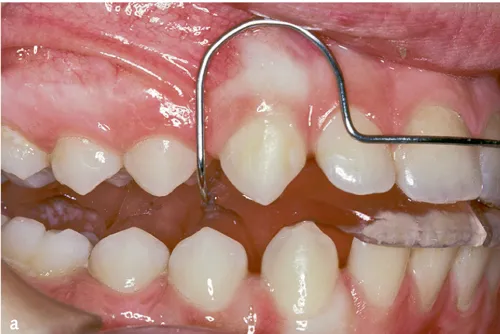

Abb. 3a bis c Intraorale Fotos von drei Aktivator-Patienten mit unterschiedlich hohen Konstruktionsbissen: a) Niedriger Konstruktionsbiss (2–4 mm)1, b) hoher Konstruktionsbiss (15–20 mm)10 und c) mittelhoher Konstruktionsbiss (5–7 mm)11.